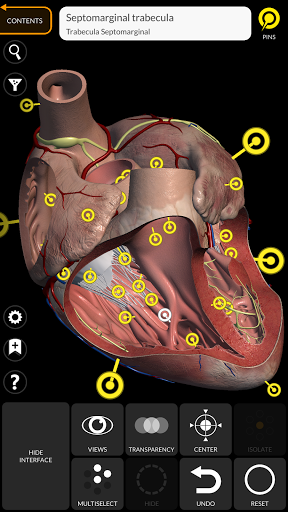

"Anatomía - Atlas 3D" permite estudiar la anatomía humana de forma fácil e interactiva.

A través de una interfaz sencilla e intuitiva es posible observar cada estructura anatómica desde cualquier ángulo.

Los modelos anatómicos 3D son especialmente detallados y con texturas de hasta una resolución de 4k.

La subdivisión por regiones y las vistas predefinidas facilitan la observación y el estudio de partes individuales o grupos de sistemas y las relaciones entre los diferentes órganos.

• Sistema cardiovascular • Sistema

nervioso • Sistema respiratorio • Sistema digestivo • Sistema urogenital (masculino y femenino) • Sistema endocrino • Sistema linfático • Sistema ocular y auditivo CARACTERÍSTICAS • Interfaz sencilla e intuitiva • Rotar y hacer zoom en cada modelo en el espacio 3D • Opción para ocultar o aislar uno o varios modelos seleccionados • Filtro para ocultar o mostrar cada sistema • Función de búsqueda para encontrar fácilmente cada parte anatómica • Función de marcador para guardar vistas personalizadas • Rotación inteligente que mueve el centro de rotación automáticamente • Función de transparencia • Visualización de músculos a través de niveles de capas desde las superficiales hasta las más profundas • Al seleccionar un modelo o un pin, aparece el término anatómico relacionado • Descripción de los músculos: origen, inserción, inervación y acción • Mostrar/ocultar interfaz de usuario (muy útil con pantallas pequeñas) MULTILINGÜE • Los términos anatómicos y la interfaz de usuario están disponibles en 11 idiomas: latín, inglés, francés, alemán, italiano, portugués, turco, ruso, español, Chino, japonés y coreano • Los términos anatómicos se pueden mostrar en dos idiomas simultáneamente REQUISITOS DEL SISTEMA • Android 8.0 o posterior, dispositivos con al menos 3 GB de RAM Reversi

• Sistema cardiovascular